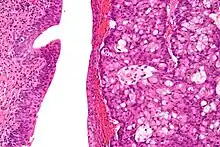

| Micrograph of urachal carcinoma (right of image) and non-malignant urothelium (left of image). H&E stain. | |

Urachal cancer usually is an adenocarcinoma (about 90%) mostly with mucinous/colloidal histology. Other rare types include urothelial carcinoma, squamous cell carcinoma, neuroendocrine carcinoma and sarcoma.[2][4][7][8]